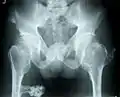

ورم عظمي غضروفي متعدد في الحوض

قد يكون أول عرض يظهر عبارة عن ورم يظهر على أحد الأطراف. يمكن أن تحدث تشوهات متعددة، وهي تشوهات حول المستوى الإكليلي الركبتين والكاحلين والكتفين والمرفقين والمعصمين. على سبيل المثال الركبة الروحاء، الكاحل الأروح، انحناء الزند وقصره، ويواجه الكوع المسحوب. غالبية الأفراد المصابين لديهم أورام عظمية غضروفية تظهر حول الركبة. وقد يصاحبة الساعد في HMO.[1][4] علاوة على ذلك قد يحدث قصر القامة ومظهر غير متجانس بشكل عام. عادةً ما تنجم هذه المظاهر عن اضطراب في النمو النمائي خاصة أن الأورام العظمية الغضروفية تنشأ عادةً عند الأطراف الكردوسية (metaphyseal) للعظام الطويلة بالقرب من الأنمية (physis). الورم العظمي الغضروفي المفصلي للورك يمكن أن يؤدي إلى الحد من نطاق الحركة وآلام المفاصل وخلل التنسج الحقي (acetabular dysplasia).[2] وبالمثل يمكن أن يحدث ألم المفاصل في أماكن أخرى ويحدث انضغاط للأوعية الدموية العصبية. علاوة على ذلك يمكن أن يكون العجز الوظيفي فيما يتعلق بأنشطة الحياة اليومية علامة. ألم التشوه الفقري أو التسوية العصبية يجب أن يثير الشكوك حول تورط الفقرات.[3]

يتميز بنمو أورام العظم الحميدة المغطاة بالغضاريف حول مناطق النمو العظمي النشط، لا سيما كردوس العظام الطويلة. عادة ما يتم العثور على خمسة أو ستة أعران في الأطراف العلوية والسفلية. المواقع الأكثر شيوعًا هي:[15]